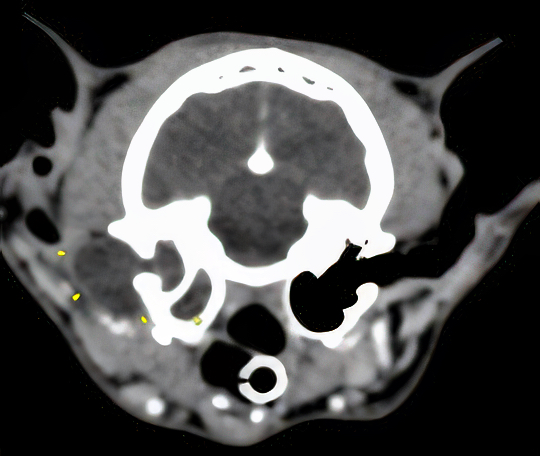

Nous présentons également un cas d'extension d'une rhino-sinusite infectieuse chez un chat présentant une ataxie. Un scanner montre des lésions naso-sinusales agressives avec lyse de la paroi sinusale frontale et empyème méningé adjacent. Une trépanation du sinus frontal permet de réaliser des prélèvements pour analyses bactériologiques et mycologiques. Un traitement antibiotique ciblé permet une bonne évolution clinique.

De ce fait, les examens d'imagerie en coupes sont essentiels pour diagnostiquer les abcès intracrâniens. Nous rapportons leur aspect au scanner mais détaillons également leurs caractéristiques à l'examen d'IRM.